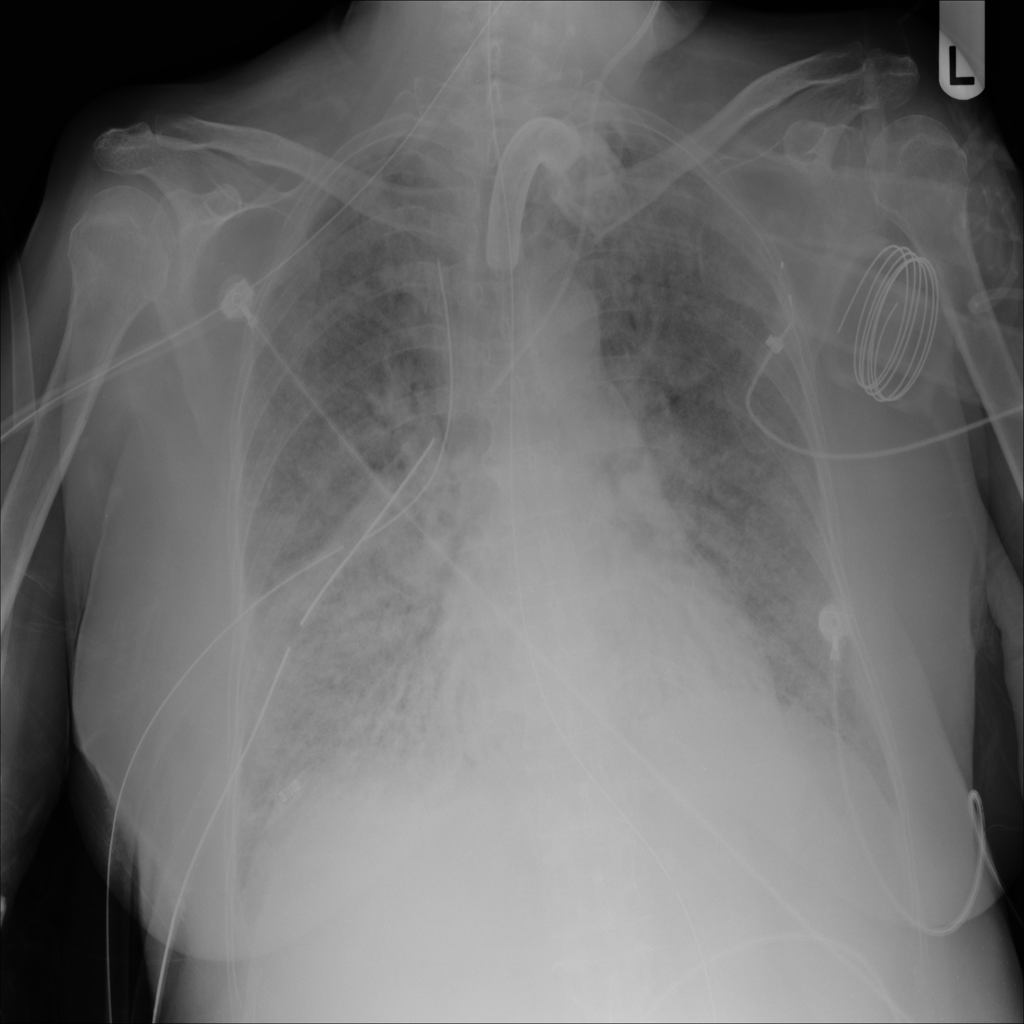

PAT-531A · IMG-006Consolidation

PAT-531A · IMG-006

PA